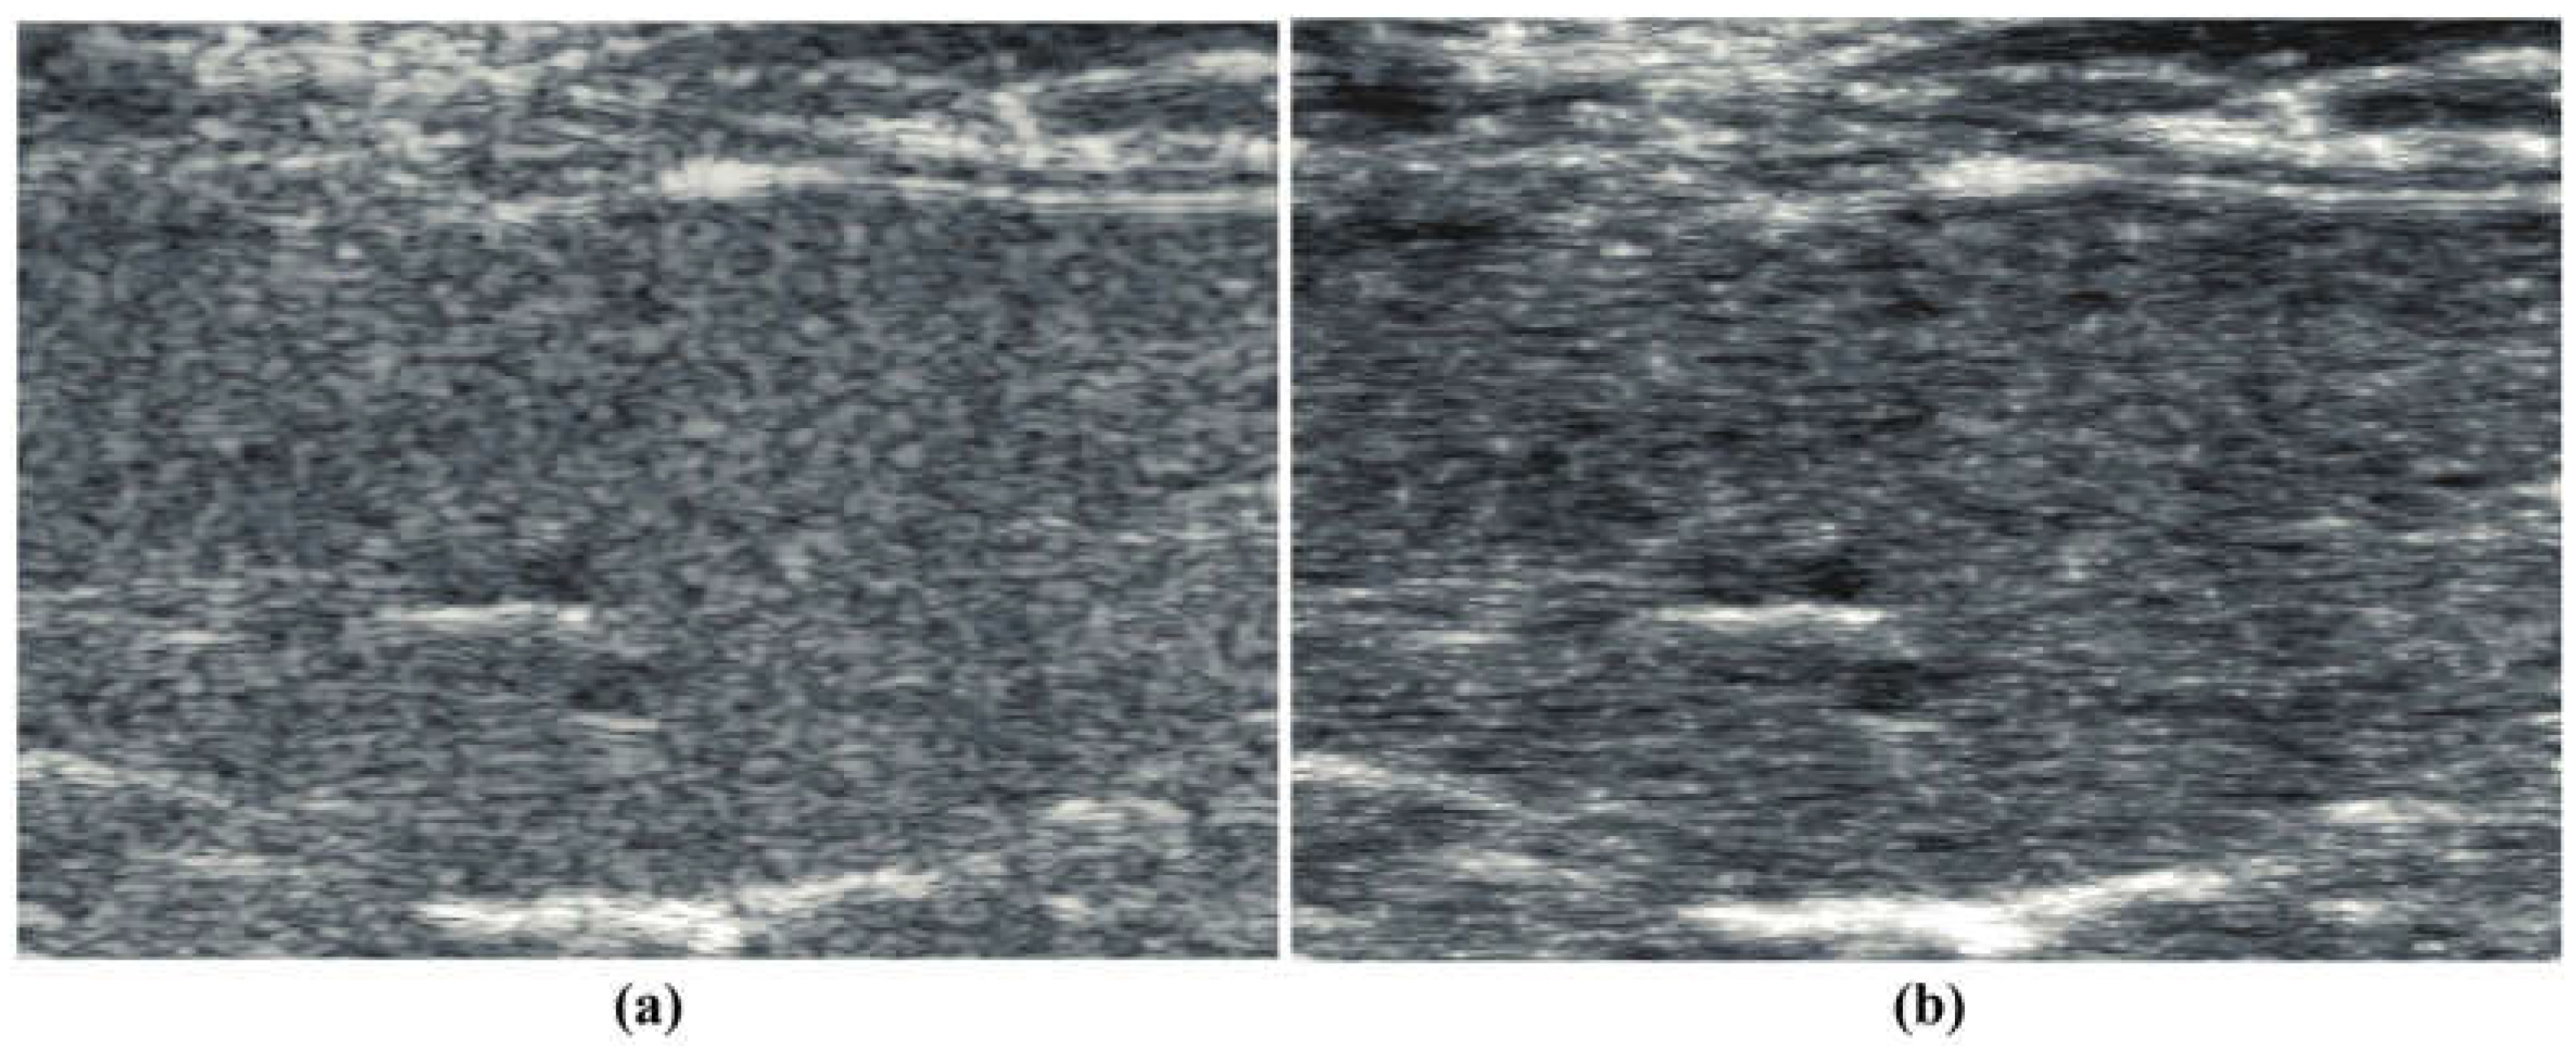

Similarly, a B-scan from a subject on a steatotic diet [19] is shown in Figure 2a, demonstrating the classic general hyperechoic pattern as compared to normals. The corresponding “thru-scan” is shown in Figure 2b. Again, a pattern of possible fluid channels (hypoechoic spaces) along with small hyperechoic foci is seen throughout the background scattering amplitude. Compared with the normal liver’s constrained reconstruction (Figure 1b), the steatotic liver in Figure 2b appears more hyperechoic, and the hyperechoic spots are distributed throughout the liver. The speckle pattern within the liver in Figure 2a from the conventional envelope has a mean/standard deviation ratio of 1.97, close to the theoretical Rayleigh speckle ratio of 1.91 expected from ensembles of subresolved scatterers [1]. In comparison, the constrained power law reconstruction of Figure 2b has a mean/standard deviation ratio of 2.18, indicating a higher value of what Burkhardt termed as the “signal to noise” ratio of speckle patterns [1]. Similar trends are seen in the processing of human livers at 3 MHz, normal vs. steatotic, but these images are not available at this time for distribution, only by request.

Figure 2.

(a) Conventional B-scan at 15 MHz from a diet-induced steatotic mouse liver, in vivo. (b) constrained reconstruction from power law principles, which we call “thru-scan”, demonstrating a modified background and the emergence of specific hyperechoic points. The images are displayed conventionally using log-compressed 50 dB dynamic range grayscale.